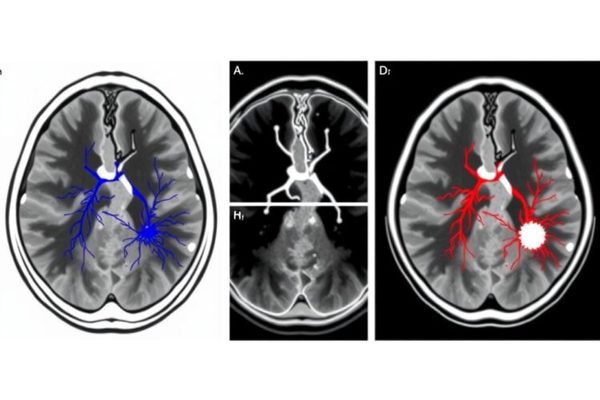

Home Science News Biology New Study Reveals Striking Parallels Between Atherosclerosis and Tumor Development June 17, 2025 in Biology Reading Time: 4 mins read 0 67 SHARES 606 VIEWS Share on